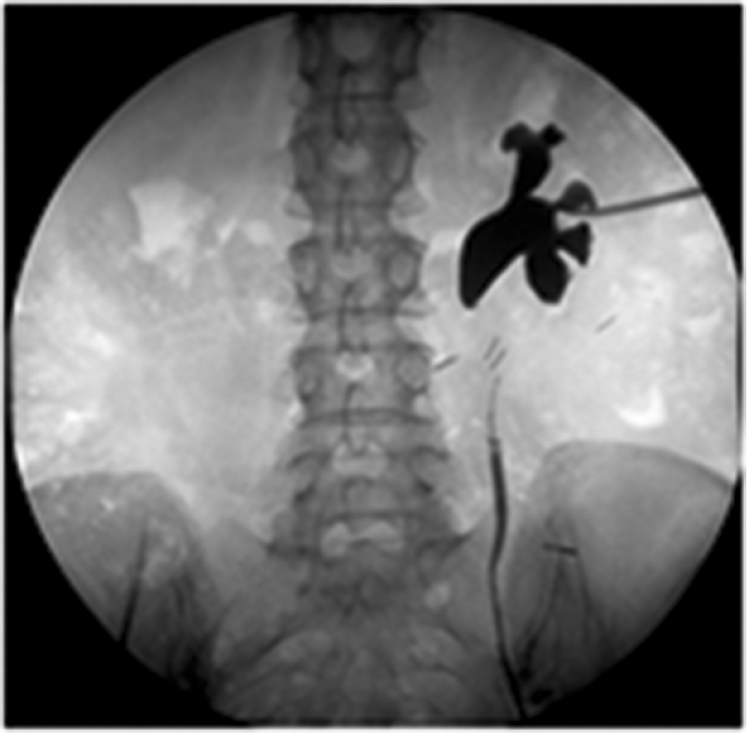

У пострадавшей с огнестрельным ранением дробью при первичной диагностике были выявлены повреждения левой почки и мягких тканей. После некрэктомии и установки нефростомы рана почки была ушита. Спустя трое суток после операции состояние пациентки ухудшилось, появились лихорадка и боли в животе. При повторном обследовании на уровне верхней трети мочеточника было выявлено поступление контрастного вещества в забрюшинное пространство (рис. 1).

Рис. 1. Огнестрельное ранение левого мочеточника

Пострадавшей повторно выполнили операцию, в ходе которой обнаружили ранение мочеточника, сопровождающееся некрозом и мочевой инфильтрацией окружающих тканей. Пациентке провели некрэктомию и перевязку мочеточника с выполнением впоследствии реконструктивного вмешательства.